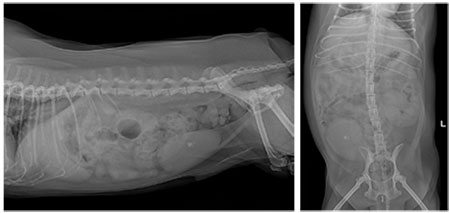

방사선 영상 상, 방광 결석이 보였다. 신장은 결석 혹은 calcification으로 보이는 부분이 있었다.